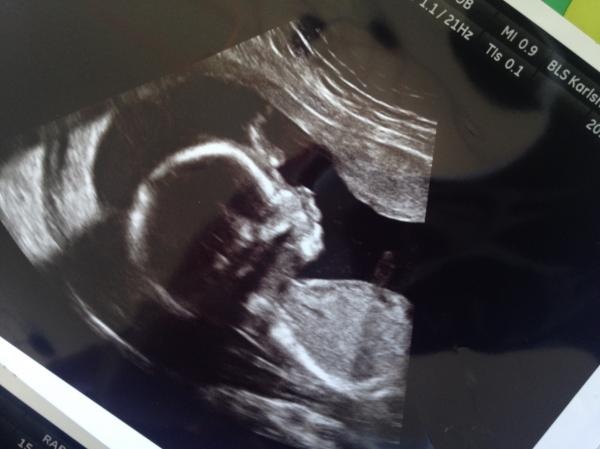

BF september 2015!

Fler som vill följas åt på resan till bebis, utbyta tankar känslor råd och allt annat!:)